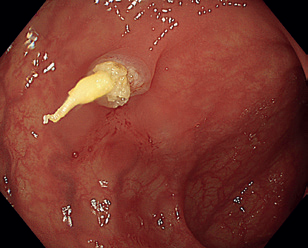

Obr. 5 Extrakce resekátu stopkatého polypu.EMR zahrnuje několik technik. Nejběžnější je technika „lift and cut“, při které se provádí submukózní injekce různých roztoků vedoucí ke zvednutí léze s následným uchopením a odstraněním kličkou (obr. 8–11). Submukózní injekce může obsahovat fyziologický roztok, glukózu a glycerol, zředěný adrenalin nebo gelatinózní látky. Pro lepší orientaci v submukóze se do roztoku často přidává modré barvivo, jako je methylenová modř nebo indigokarmín. Zvednutí léze dané rozšířením submukózy se označuje jako „lifting.“ V případě fibrózy nebo hluboké nádorové invaze dochází k „liftingu” jen částečně nebo vůbec, odstranění léze je poté obtížné až nemožné.